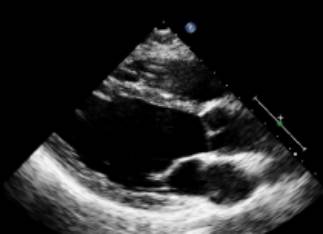

图|胸骨旁左心长轴切面,二尖瓣瓣尖水平。左图为舒张末期,右图为收缩末期。

随着图像处理技术的改进,已经提高心脏结构的分辨率。可按照真实的组织和血流的界面来测量室间隔和左心室后壁的厚度,而不是像以前测量前缘回声之间的距离。

ASE推荐于二尖瓣瓣尖水平胸骨旁短轴切面直接测量或采用M型曲线测量。M-型超声时间分辨率好。有助于帮助二维超声区分临近左室后壁的肌小梁、室间隔左室面的假腱索、室间隔右室面的调节束等结构。即使采用二维引导也可能无法保证M-型取样线完全垂直于室间隔和左心室后壁。